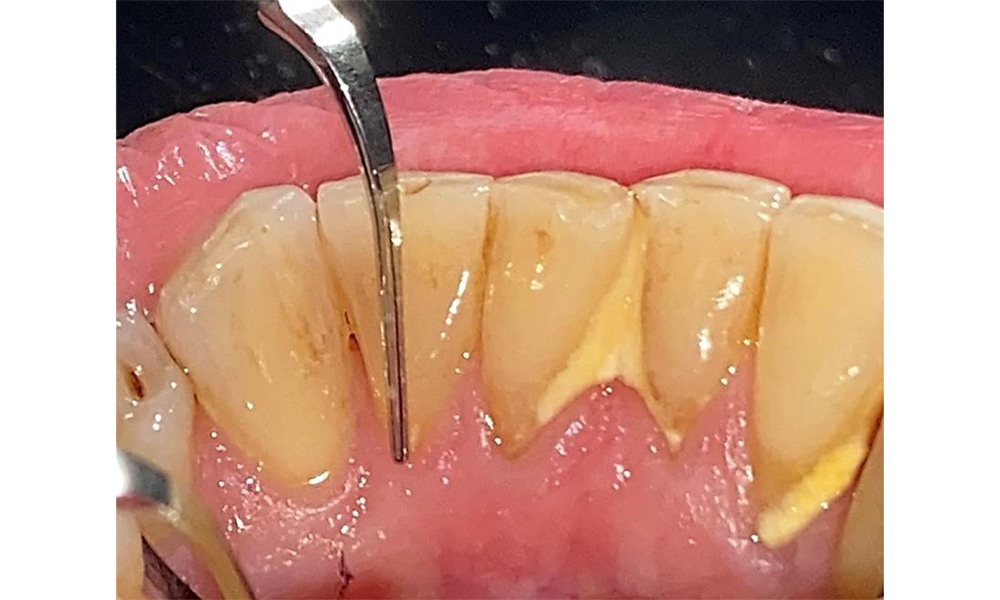

Occlusal view of the mandible showing the denture in situ.

Fig. 6 Occlusal view of the mandible showing the denture in situ. © Dr R. Krapf

The patient uses interdental brushes and an electric toothbrush. This demonstrates good compliance and good intraoral hygiene behaviour and understanding at home. Regular motivation and re-instruction are indispensable due to the risk of progression, particularly with regard to the cleaning of interdental areas, since increased probing depths were detected in these areas. Localized calculus and soft plaque was present in the lingual anterior mandibular region, and these must be shown to the patient. The interdental brush size may need to be checked and adjusted. A soft brush attachment is recommended based on the presence of exposed root surfaces to prevent wedge-shaped defects. Toothpaste with a low abrasive value should be used.

There are no limitations regarding the choice of instrumentation methods. Regular supragingival and subgingival instrumentation is essential to prevent disease progression due to the pre-existing periodontitis and high risk of recurrence. There are no limitations placed on the selection of instruments for mechanical biofilm removal from a general medical perspective, and removal should be performed as needed. Hard and mineralized plaque, such as calculus and concretions, should be removed using manual instruments or sonic/ultrasonic scalers (Fig. 9) (8, 9).

Use an ultrasonic tip to remove hard, mineralized plaque (Proxeo Ultra scaler with the Perio tip, W&H, shown here).

Fig. 9: Use an ultrasonic tip to remove hard, mineralized plaque (Proxeo Ultra scaler with the Perio tip, W&H, shown here). © Dr R. Krapf